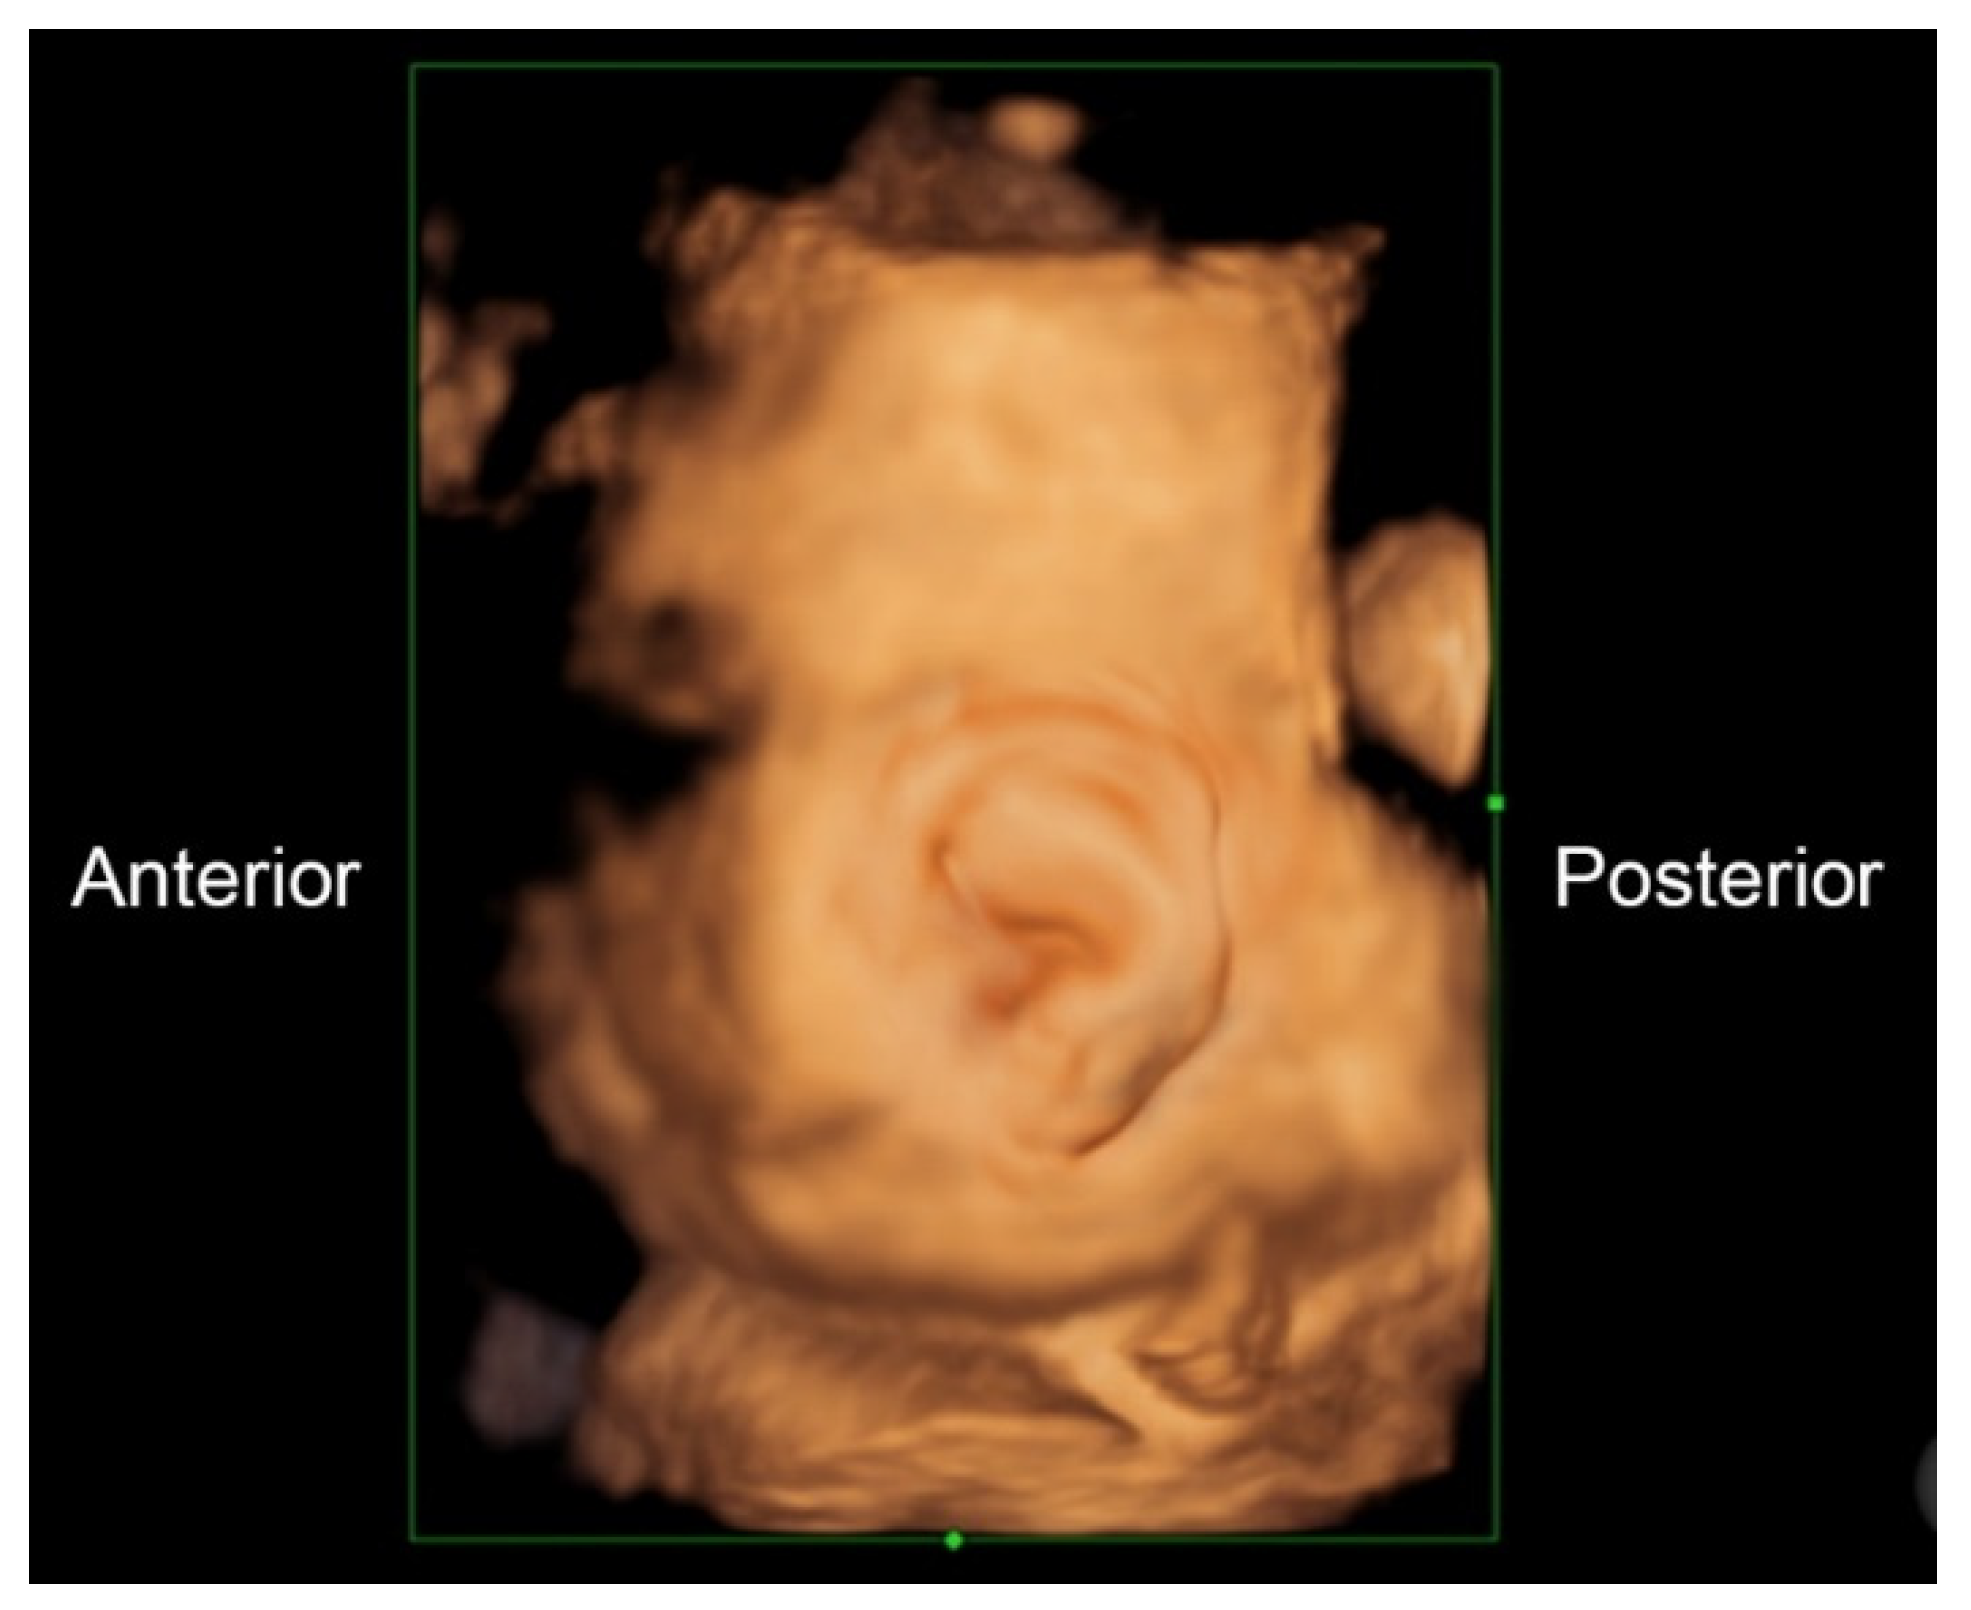

A 32-year-old pregnant woman, G4 P2102, attended her first visit of antenatal care at 23+3 weeks of gestation. Ultrasound examination for anomaly screening demonstrated cardiac defects, including double-outlet right ventricle: DORV-TOF type, with severe pulmonary stenosis (Figure 1) and left superior vena cava. Detailed ultrasound showed no associated abnormalities. Fetal biometry was consistent with gestational age except abdominal circumference and estimated fetal weight, which were relatively low (at 10th percentile), reflecting some degree of growth restriction. However, detailed ultrasound on the follow-up scans at 28 weeks of gestation showed subtle abnormalities, including malrotation of both kidneys, the hilum or renal pelvis facing posteriorly to the abdominal wall (Figure 2). Furthermore, 3D-ultrasound revealed abnormal external ear structure (markedly prominent crus of anti-helix) (Figure 3). Non-stress tests (NST) showed spontaneous fetal heart rate (FHR) accelerations (normal reactive tests) (23+3 weeks). Interestingly, the fetus showed persistent non-response to acoustic stimulation tests at 26, 30, 32, 36 and 38 weeks (no FHR accelerations as well as no quickening perceived by ultrasound) (Figure 4), probably reflective of auditory dysfunction. Based on the findings of heart defect, ear defect, renal defect and growth restriction, several differential diagnoses were listed, including CHARGE syndrome. Theoretically, fetal blood sampling for molecular genetic tests should be performed. Nevertheless, since no lethal condition was identified and the couple wanted to continue pregnancy regardless of investigation results, prenatal invasive diagnosis was avoided, and we waited for postnatal work-up instead. She had no significant underlying disease and no familial history of hereditary diseases. Her pregnancy was uneventful except that she developed gestational diabetes (GDM) at 28 weeks of gestation, which was well-controlled with diabetic diet.

Figure 3.

3D-Ultrasound: Abnormal ear; markedly prominent superior crus of anti-helix.

Ear structural abnormality in our case was first subjectively diagnosed, but it seems to be more significant when combined with its function. As already known, fetuses are very sensitive to acoustic stimulation, routinely used in antenatal surveillance, leading to FHR accelerations and fetal quickening. We took advantage of this stimulation to test the auditory perception. Because the fetus persistently showed no response to acoustic stimulation, either by FHR acceleration or quickening in spite of having spontaneous FHR acceleration and quickening, it may reasonably be concluded that the fetus was likely to have auditory dysfunction, probably associated with structural abnormality of the ear canal and external ear abnormality, as seen on 3D-ultrasound.